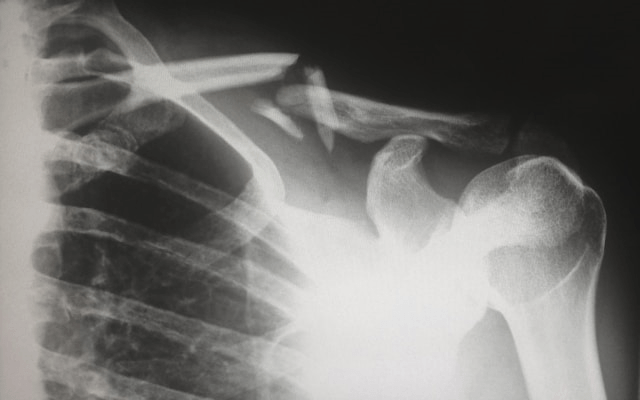

鎖骨がかなり複雑骨折なのに、薬漬けで放置みたいなレベルが、日本の精神科医療の現在地です。先進国では日本だけです。きちんと勉強をしました。先進国では日本だけです。ここまで杜撰な治療を標準治療として、日本の精神科医が治療基準を定めている国は、日本だけです。

減薬のそれぞれの方法が、複雑骨折に患者側で出来る精一杯の手当てになったり、コルセットになったり、きっとするんだと思います。